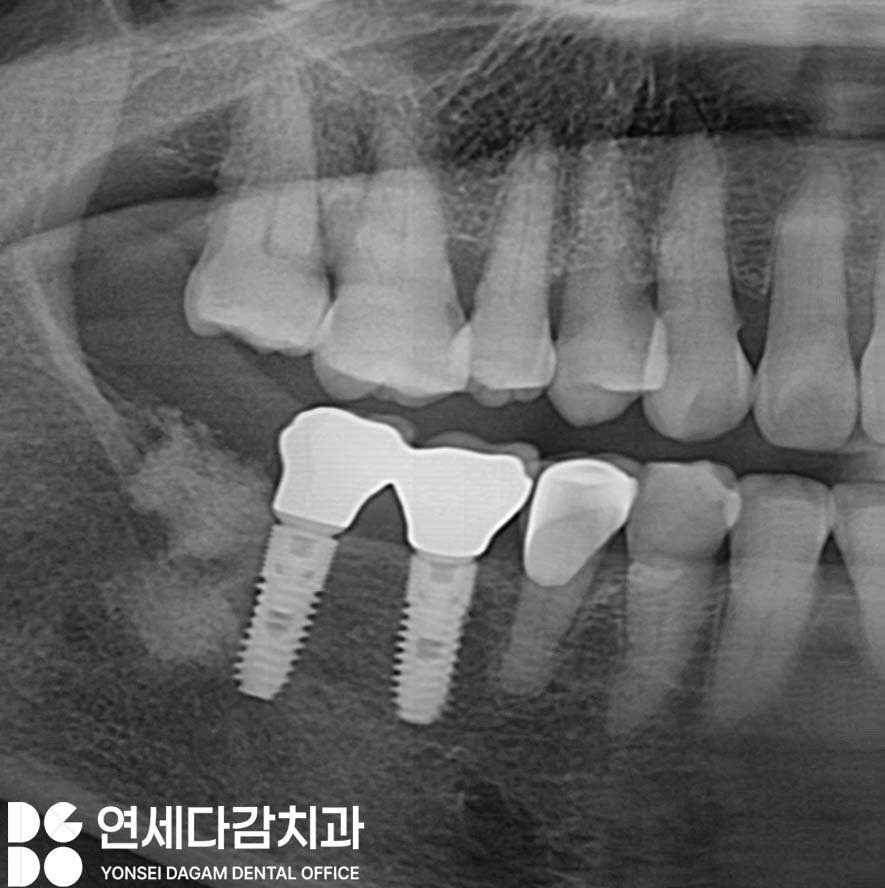

오래된 보철물의 screw를 빼고 보니

문정동 치과 에서 육안으로 보기에

external octa fixture라고 생각했습니다.

(8각형 모양의 연결 부위가

외부로 돌출되어 있는 타입)

그러나 겉모습만으로는 정확한

구조를 파악하기는 어렵기 때문에

이런 상황에서는 치근단 엑스레이를

찍어서 임플란트의 내부 구조를

정확히 확인합니다.

확인 결과 스크류가 하나 더 있는 것을

알 수 있었습니다.